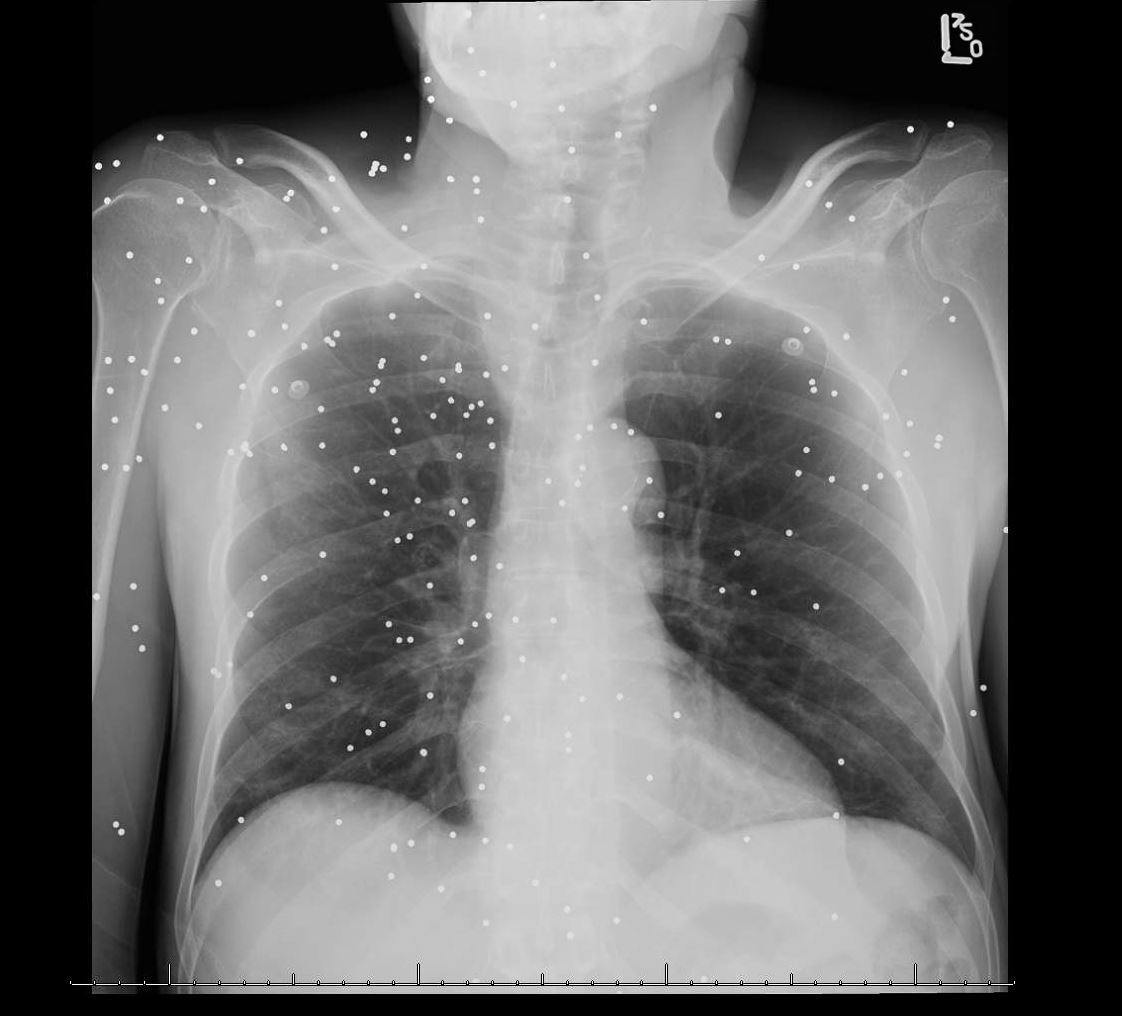

Pitting oedema to the umbilicus

68yo lady presented with bilateral leg swelling and orthopnoea. She had pitting oedema almost to...